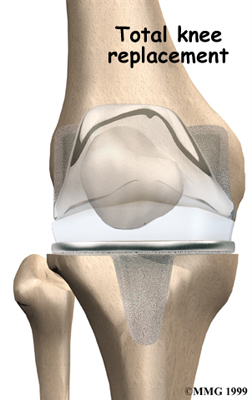

Artificial Knee Replacement

An artificial knee replacement is the ultimate solution for advanced knee OA.

Surgeons prefer not to put a new knee joint in patients younger than 60. This is because younger patients are generally more active and might put too much stress on the joint, causing it to loosen or even crack. A revision surgery to replace a damaged prosthesis is harder to do, has more possible complications, and is usually less successful than a first-time joint replacement surgery.

Related Document: FYZICAL Belmont's Guide to Artificial Joint Replacement of the Knee